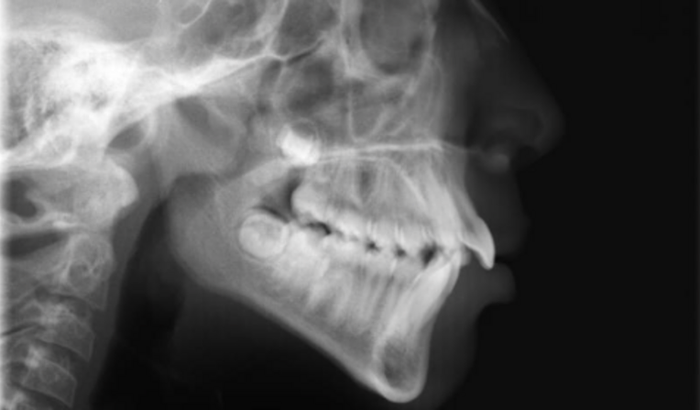

Sou mãe da Emanuelly de 9 anos, somente os mais próximos sabem,mais a Manu precisa urgente usar um aparelho para abertura do céu boca, alinhamento de dentes(ah mais pke não procurou um mais em conta? Pois bem procurei,ela até começou um tratamento,mais sem sucesso,pke toda vez que apertava o aparelho caia e meu dinheiro foi pro ralo) então me indicaram Dr Jefferson, fui até seu consultório e foi super atencioso,me explicou que o caso da Manu é mais grave que só um dente torto,esta imagem da pra ter uma noção( tenho outras fotos pra quem se interessar só chamar que mando), Manu está tendo problemas com respiração,não consegue respirar pelo nariz por conta do céu da boca muito aberto,então precisa urgente do uso do aparelho para esse fechamento e conseguir voltar a respirar pelo nariz, Manu vive com a garganta infeccionada por conta da má respiração,e como alguns sabe ela não pode ter infecção por conta da Síndrome dela(Síndrome Nefrotica/problema renal)pois cada vez que ela tem uma infecção ela incha rosto, abdômen,pernas…Eu não tenho condições e nem de onde tirar o dinheiro desse tratamento, por isso fiz essa vaquinha para que com a ajuda de todos eu possa pagar esse tratamento para ela, meu telefone é 14 998528646 estou a disposição para qualquer dúvida.. Agradeço desde já a cada um que ajudar de coração.. Deus abençoe grandemente ❤️ Obs: Se conseguirmos mostrarei o resultado e todo processo em minha rede social:LaisMota para que vcs possam ver cada passo desse tratamento… obrigada mais uma vez….